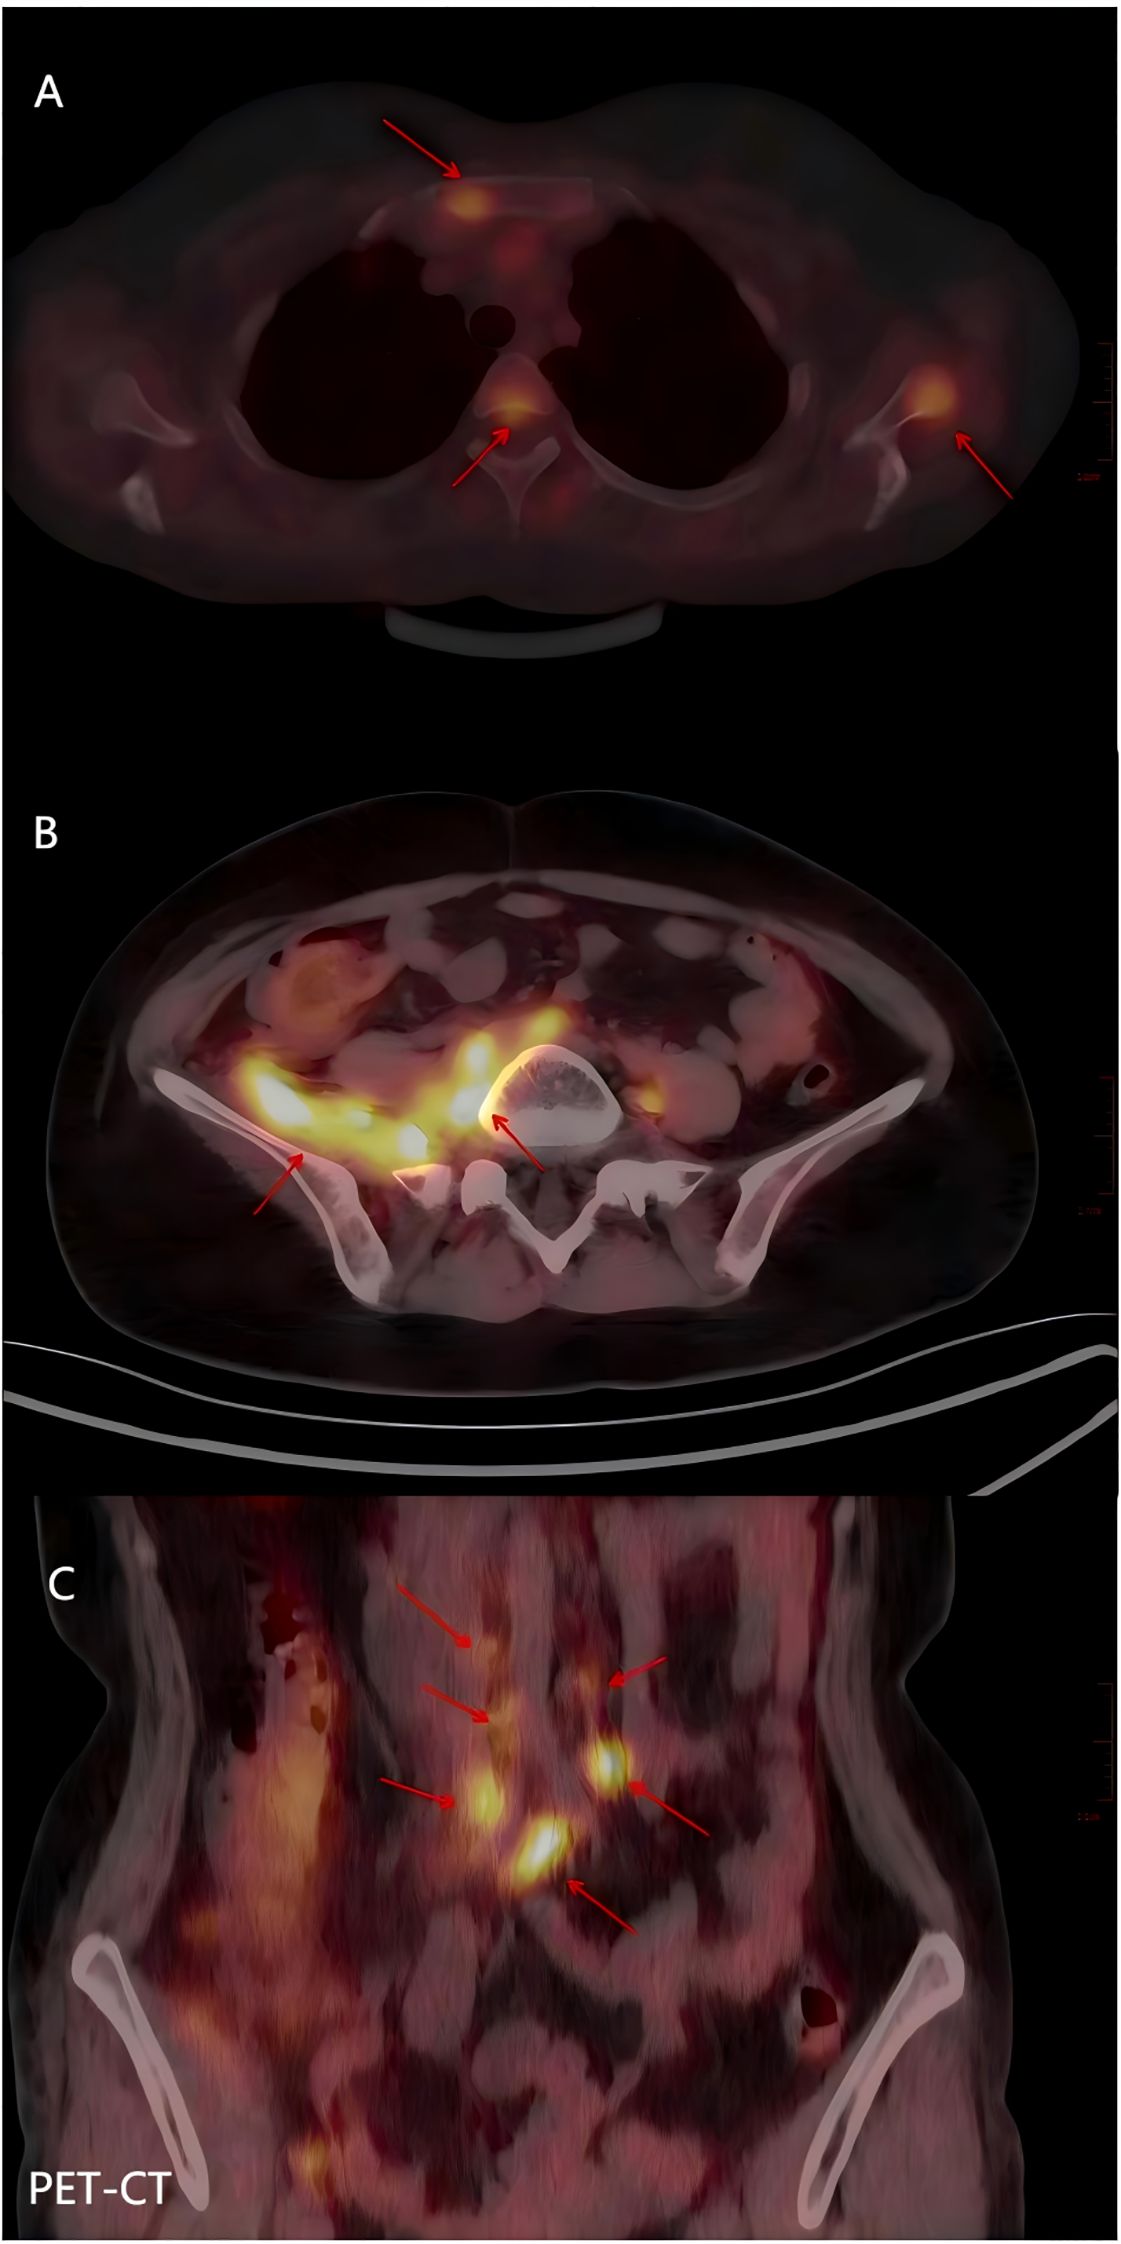

This article reports an extremely rare case of a 31-year-old pregnant woman diagnosed with large cell neuroendocrine carcinoma (LCNEC) of the cervix complicated by syndrome of inappropriate antidiuretic hormone secretion (SIADH). Admitted at 35⁺ ¹ weeks gestation due to vaginal bleeding, she was diagnosed with cervical LCNEC and pelvic lymph node metastasis. Following cesarean delivery, she developed severe hyponatremia (as low as 92 mmol/L) leading to coma during chemotherapy, meeting the criteria for SIADH. The hyponatremia was successfully corrected with the selective vasopressin V2 receptor antagonist tolvaptan. The patient subsequently achieved complete remission (CR) after concurrent chemoradiotherapy. However, the disease recurred with multiple metastases six months later. Despite multiple lines of therapy, she succumbed to multiple organ failure 19 months after initial diagnosis. This case highlights the highly aggressive nature and poor prognosis of LCNEC complicated by SIADH during pregnancy. Tolvaptan proved effective for the associated refractory hyponatremia but required careful monitoring to avoid sodium overcorrection. Dynamic serum sodium monitoring may serve as a potential biomarker for tumor recurrence. A review identified deficiencies in the management, including initial insufficient investigation into the cause of hyponatremia, aggressive fluid therapy exacerbating the condition, and delays in multidisciplinary collaboration and systemic therapy. This case underscores the critical importance of multidisciplinary collaboration and early, aggressive systemic treatment in managing such complex and rare malignancies.